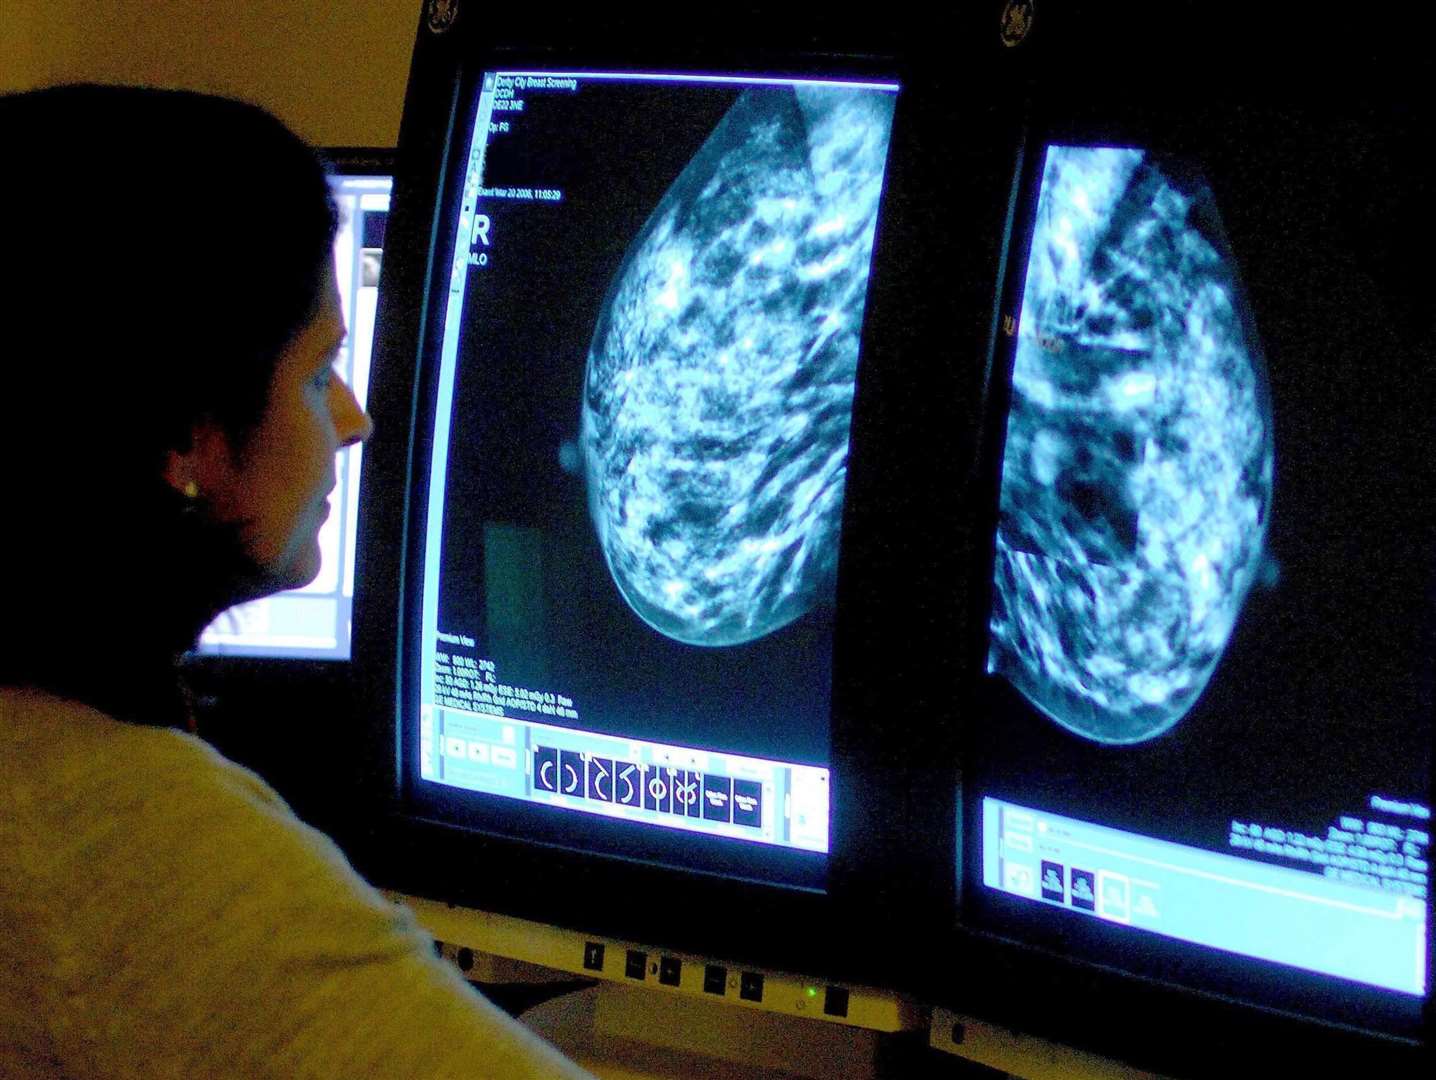

5. Двойное тестирование на рак молочной железы

Команда экспертов по искусственному интеллекту и ученых-онкологов создала платформу искусственного интеллекта, которая может обнаружить практически незаметные различия во внешнем виде раковых клеток. Эти различия позволяют получить важную информацию о молекулярном состоянии клеток, что, в свою очередь, может помочь выбрать наиболее подходящее лечение.

Рак молочной железы является наиболее часто диагностируемой причиной смерти от рака среди женщин. Врачи, использующие платформу анализа изображений PANProfiler компании Panakeia, могут в течение 15 минут получить информацию, которая поможет им принять решение о лечении рака молочной железы, вместо того чтобы ждать результатов лабораторных анализов несколько дней или даже недель. Недавно система была одобрена для использования в Великобритании и Европе.

"Эта захватывающая технология способна сэкономить лабораторные ресурсы, а также улучшить время получения результатов биомаркеров для пациентов с инвазивным раком молочной железы", - говорит Сара Пиндер, профессор патологии молочной железы в Королевском колледже Лондона.

Компания Panakeia планирует развивать свою технологию для борьбы и с другими видами рака.